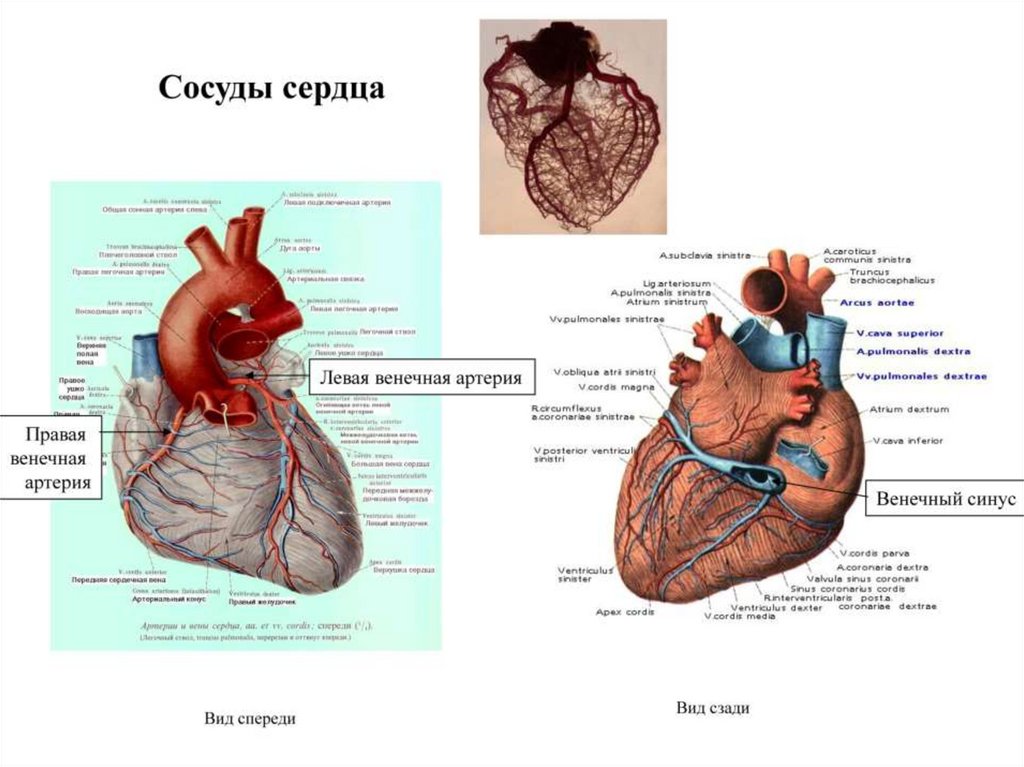

Пороки сердечно-сосудистой системы: виды и признаки